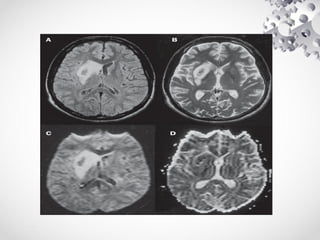

TUMORES E METÁSTASES

• NO EXAME DE RM PARA ESTUDO DE TUMEORES E MATASTASES

REALIZAMOS TODO ESTUDO DE ROTINA ACRESCENTANDO NO ESTUDO A

CRITÉRIO MÉDICO A ESPECTROSCOPIA MULTI-VOXEL E O ESTUDO

PERFUSIONAL DA LESÃO, ESTES ESTUDOS DEVERÃO SER ADOTADOS

APENAS EM LESÕES PRIMÁRIAS DO ENCÉFALO, NO CASO DE METÁSTASES

ALÉM DO ESTUDO DE ROTINA DEVEREMOS ACRESCENTAR UM CORONAL T1

COM SATURAÇÃO DE GORDURA (FAT SAT), PARA EXCLUIR A POSSIBILIDADE

DE LESÕES METASTÁTICAS NA CALOTA CRANIANA.